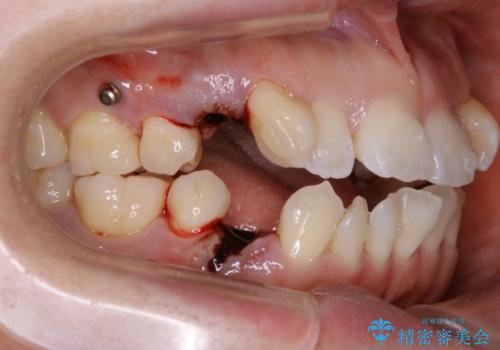

- 前歯のガタつき・噛み合わせの不調を主訴にご来院されました。

患者様のお仕事柄、目立たない装置で矯正したいとのご要望があり、今回はインビザラインを用いて抜歯矯正を行うこととなりました。

本来、抜歯によって得られる大きなスペースのコントロールはワイヤー装置の方が得意とされていますが、こちらの患者様のように犬歯が大きく手前に傾斜していて奥歯の噛み合わせにそれほど問題がないケースではマウスピース装置でも十分にコントロールできることが予測されます。

- 税込 ¥1,045,000- (インビザライン コンプリヘンシブパッケージ + マイクロインプラント費用)費用は治療当時の料金となります